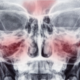

Toothache is a common problem that many people experience at some point in their lives. While it is typically felt in the mouth and jaw, it can also cause discomfort in other parts of the body, including the head.

There are several ways in which toothache can cause headache. One of the most common is through referred pain. This occurs when pain in one part of the body, such as a tooth, is felt in another part of the body, such as the head. This is because the nerves in the face and jaw are connected to the same nerves that supply the head and neck.

Another way in which toothache can cause headache is through tension. When a person is in pain, they may unconsciously clench their jaw or tense the muscles in their head and neck. This tension can cause headache and further exacerbate the toothache.